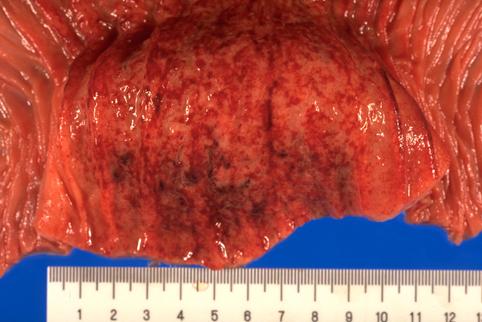

clasificación del pacienteTumor Maligno del Sistema Linfático/Linfoma Maligno

parte(separada por órganos)intestino delgado/yeyuno

método de exámenMacro

diámetro mayor del tumor40 -

grado de penetracións(a)